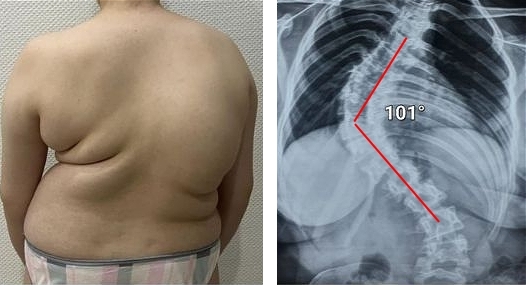

Podívejte se na tuto fotografii. Je to páteř člověka jen ve 44 letech, ale vypadá jako u starého člověka. Dříve se takové destrukce objevovaly po 60, dnes jsou běžné už u těsně nad 40. Tyto změny se s věkem zhoršují a jejich ignorování znamená riziko úplné ztráty pohyblivosti!

Páteř 44letého pacienta: vše začalo prostou bolestí, ale během týdne se objevila kýla, o dva týdny později posunutí obratlů, stlačení nervů a invalidní vozík.

Podívejte se na tyto fotografie. To se stalo těm, kdo příznaky ignorovali. Dnes jsou bezmocní a mnoho z nich nemá na koho se o péči spolehnout. Opravdu chcete takový osud?

Žena, 52 let. Závažné posunutí a deformace meziobratlových plotének se stlačením nervů a poškozením míchy.

„Vdovský hrb“ — deformace obratlů a neustálá nesnesitelná bolest, která se každým dnem zhoršuje.